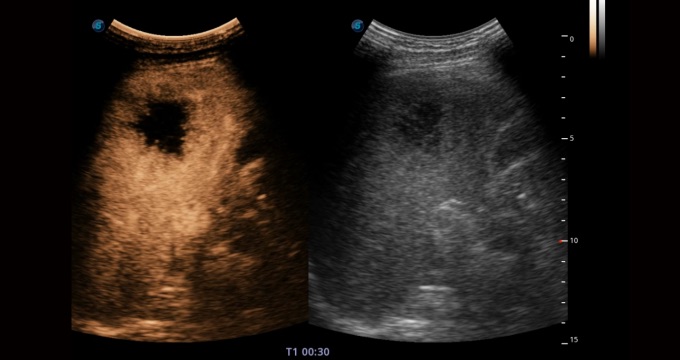

腹部應(yīng)用

造影成像功能和定量分析工具包使醫(yī)生能夠準(zhǔn)確的評(píng)估血流灌注情況。獨(dú)特的動(dòng)態(tài)聲壓控技術(shù)有效控制造影劑的聲壓,保證造影劑持續(xù)時(shí)間,方便醫(yī)生觀察病變灌注的延遲相位。